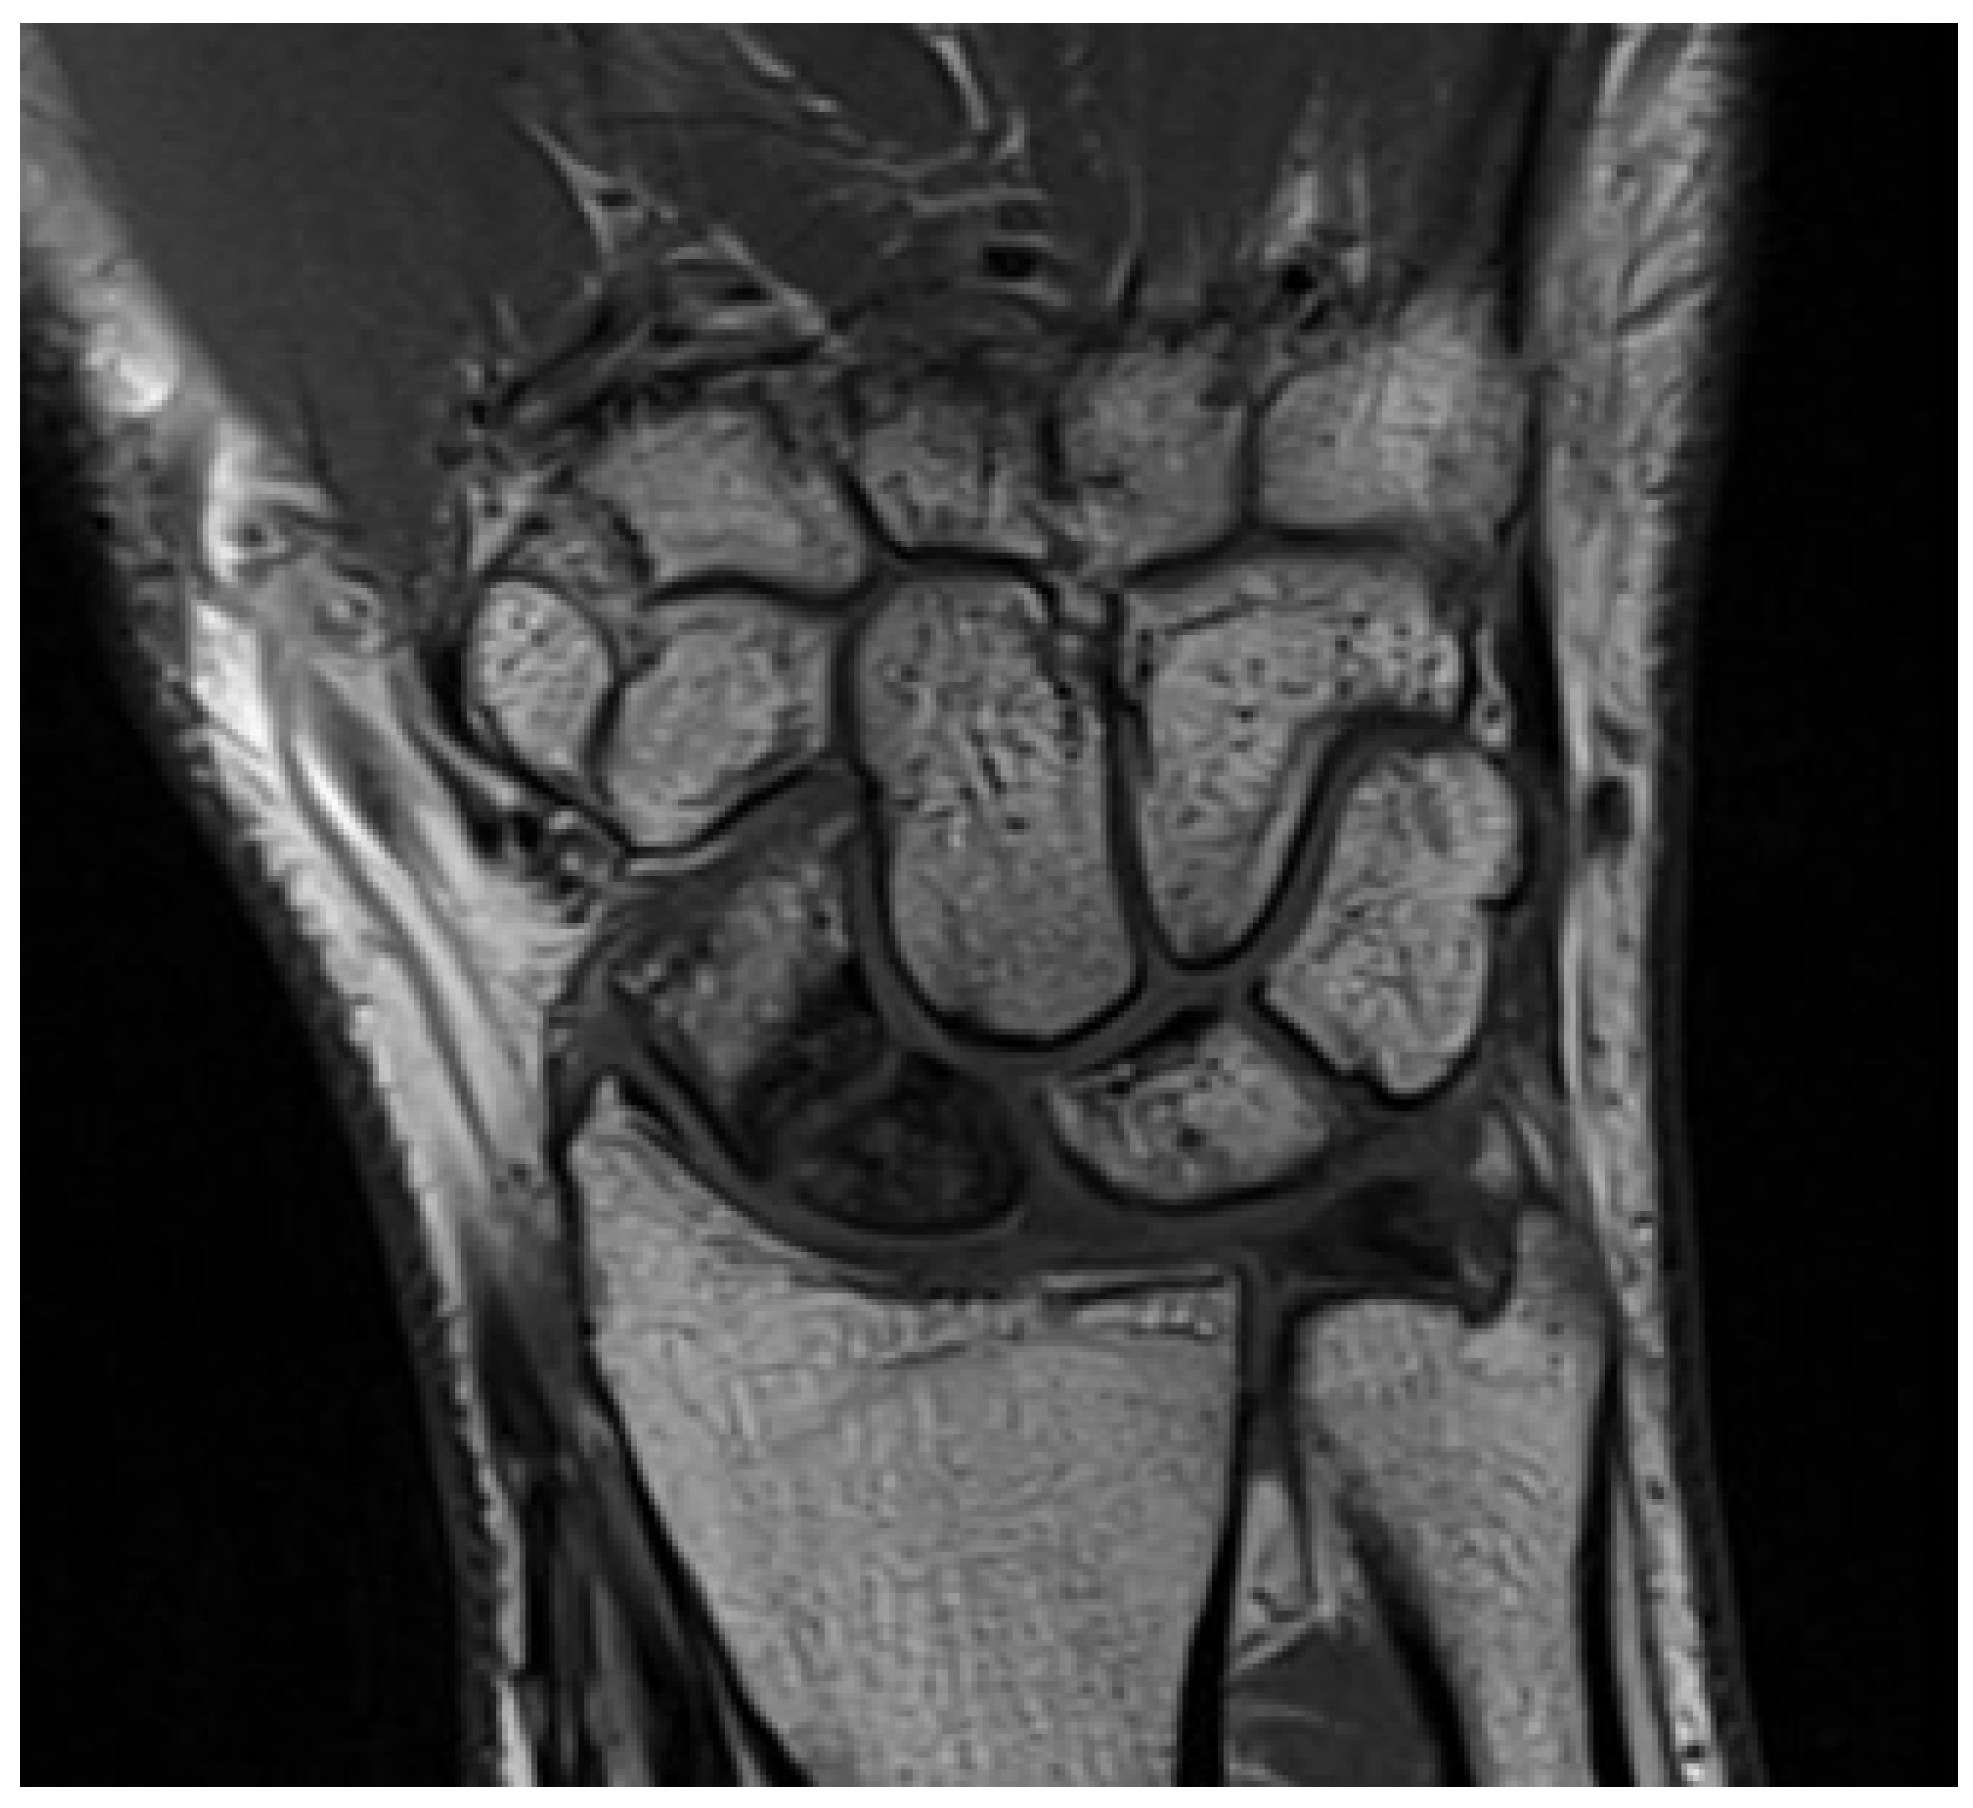

5.2. Magnetic Resonance Imaging (MRI)

| Magnetic resonance imaging (MRI) | Excellent soft tissue resolution; Differentiation of acute from chronic injuries; Non-invasive and preferred for soft tissue assessment [24]. | Diagnosis of TFCC tears and associated abnormalities; Assessment of structures involved in DRUJ stability; Identification of bone contusions and soft tissue injuries [12,24]. |